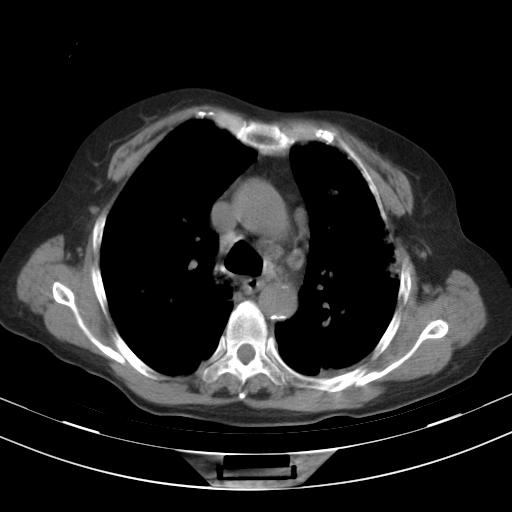

老年女性,嗜睡3天,意识模糊。轻咳,无发热。

1)两肺感染性病变;建议抗炎治疗后复查。2)纵隔淋巴结肿大。3)左侧胸腔积液。

2)纵隔淋巴结肿大。